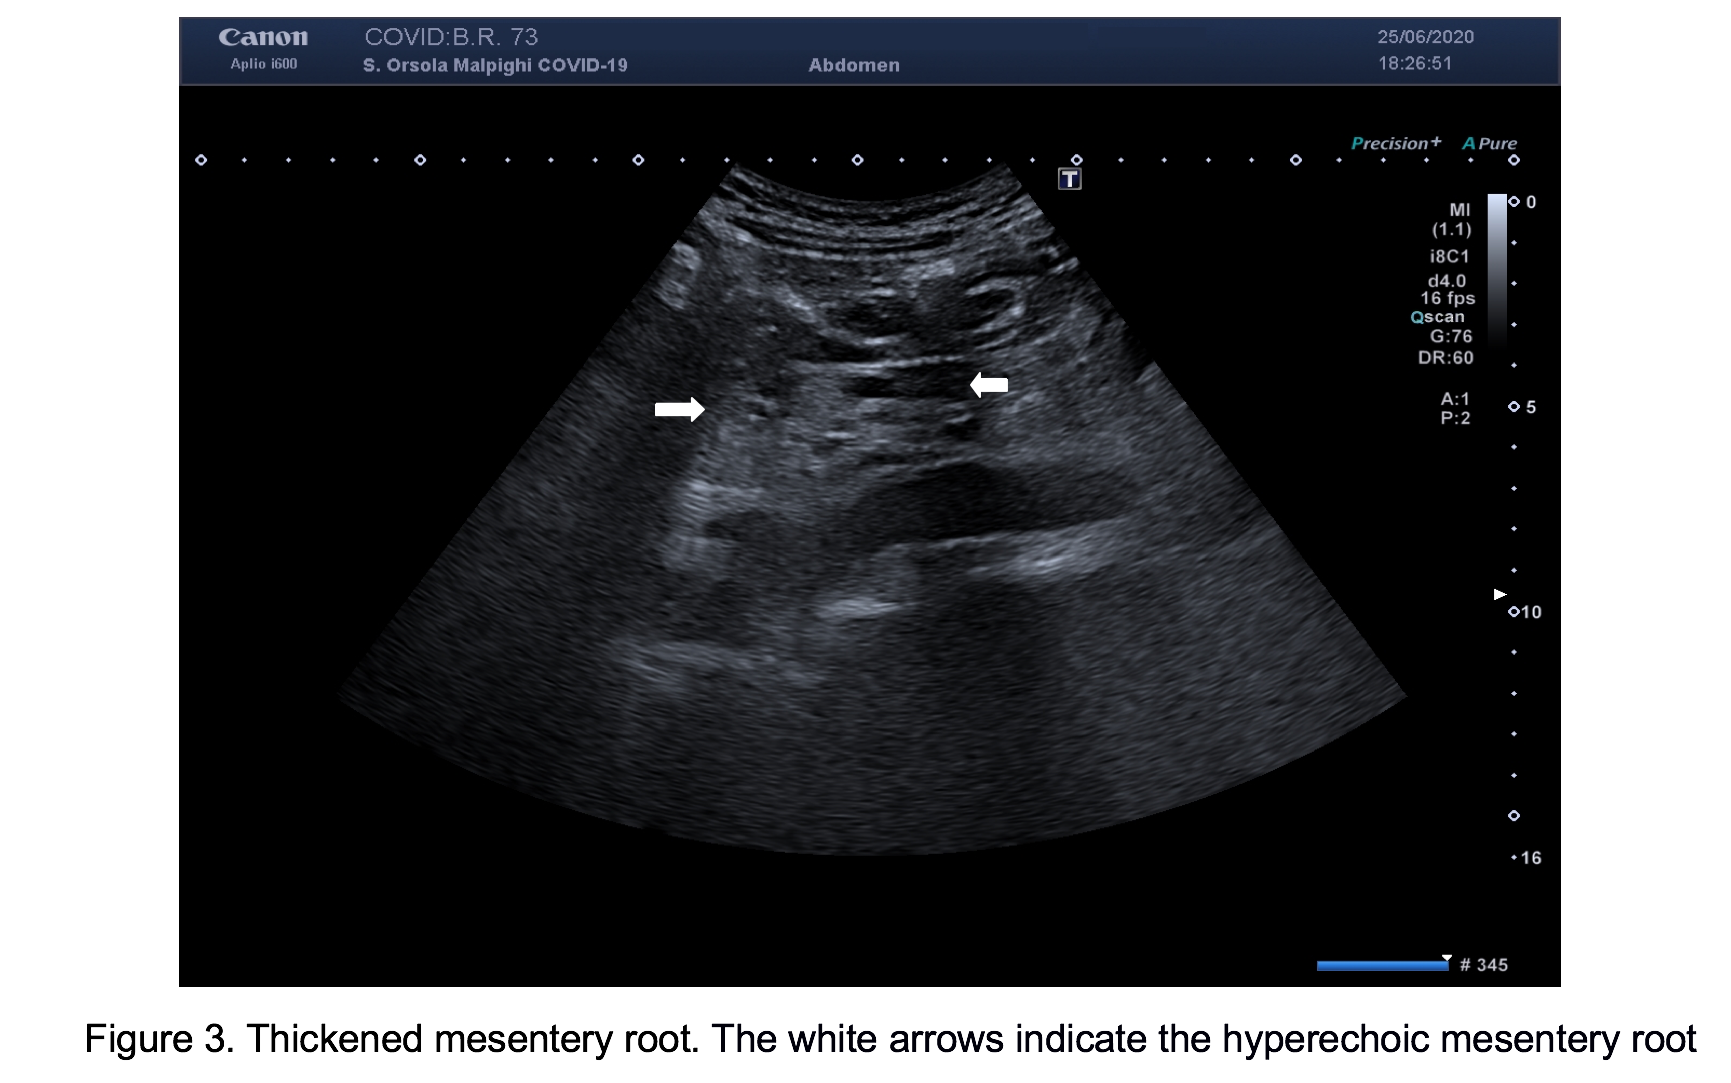

For persistent abdominal pain, we performed bowel ultrasound that showed, in both patients, dilated fluid-filled bowel loops with mildly thickened wall (3-4 mm), in different quadrants of the abdomen (Figure 1). Moreover, the mesenteric root appeared thickened and hyperechoic, with hypo-echogenicity of the adjacent retroperitoneal and meso-colonic fat, with a typical “mass effect” , suggestive of a mesenteritis. The bowel loops and the mesentery root however, did not show increased vascular flow with Colour Doppler and there was no free fluid in the abdomen (Figures 2 & 3; Video 1).

In these two patients, bowel ultrasound showed findings similar to patients with a mesenteritis, suggesting that COVID-19 could also cause inflammation to mesentery with consequent abdominal pain. Further research of patients with COVID-19 and GI symptoms are suggested to confirm these observations and to evaluate the clinical impact of bowel US in this setting.